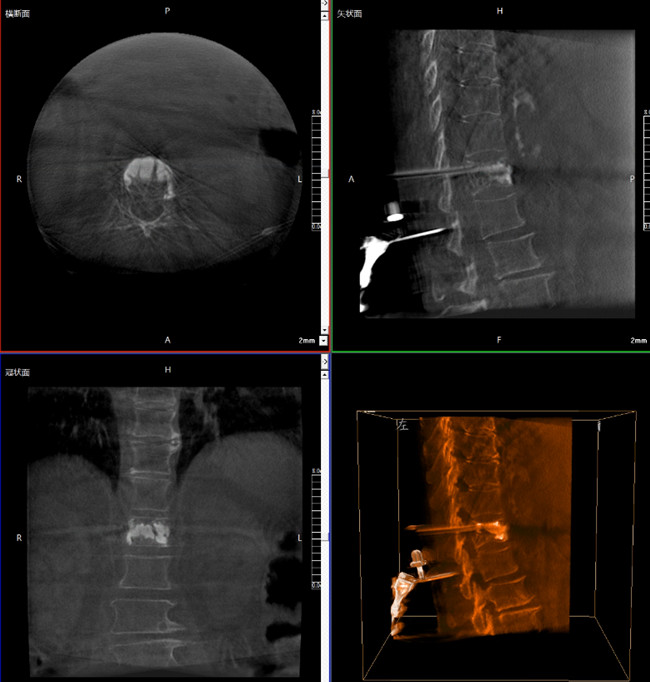

? 手術(shù)效果確認(rèn)

*骨水泥置入效果良好

良好的臨床使用體驗(yàn)源于普愛醫(yī)療骨科機(jī)器人導(dǎo)航系統(tǒng)和醫(yī)生的完美配合。亞毫米級的準(zhǔn)確定位、直觀的術(shù)前規(guī)劃和機(jī)械臂的執(zhí)行,使醫(yī)生無需擴(kuò)大創(chuàng)口進(jìn)行傷椎入針路徑定位,僅需術(shù)前三維重建即可全方位了解傷椎位置及穿刺路徑,除了極大的提高了一次性穿刺成功率,也大幅降低了手術(shù)對醫(yī)生經(jīng)驗(yàn)的要求,手術(shù)上手難度更低。